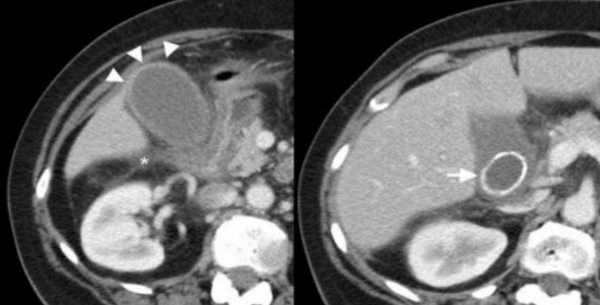

УЗИ и КТ желчного пузыря. Ксантогранулематозный холецистит. Слева на УЗИ визуализируется (помечено стрелками) утолщение стенки желчного пузыря с интрамуральным включением и с камнем в просвете органа. Справа на КТ выявляется утолщение стенки с гиподенсными включениями.

Выше представлено КТ пациента 71 года с ксантогранулематозным холециститом. Постконтрастное КТ. Визуализируется утолщение стенки желчного пузыря с включениями, которые соответствуют абсцессу или фокусам воспаления.

УЗИ (слева) и КТ (справа) желчного пузыря. На УЗИ ярко выраженное утолщение стенки желчного пузыря (указаны белыми стрелками). Множественные камни в просвете желчного пузыря (указано стрелкой). Компьютерная томография с контрастным усилением. На КТ визуализируются утолщение стенки с внутристеночными гиподенсными включениями. На КТ также выявлено, что процесс распространился на печень (указано стрелкой).